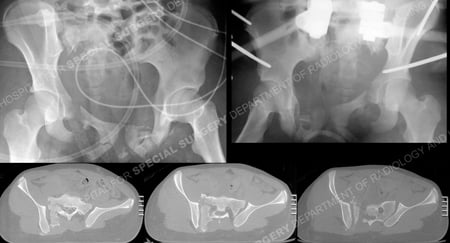

Pelvic radiograph obtained following the injury (top left image) and following placement of pelvic external fixation (top right image) and CT scan images (bottom images).